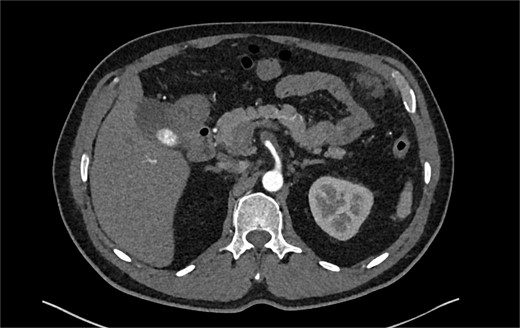

Despite medical management, the patient continued to have episodes of abdominal pain following discharge. One month after discharge, an outpatient mesenteric angiogram showed persistent SMA dissection and pseudoaneurysm. Coil embolization was performed to resolve the pseudoaneurysm. Following the procedure, the patient resumed anticoagulation therapy. The patient continued to follow outpatient studies with CTA indicating a normal SMA status post coil embolization of the pseudoaneurysm (Fig. 3).

CTA demonstrating interval embolization of SMA at site of prior thrombus and dissection.